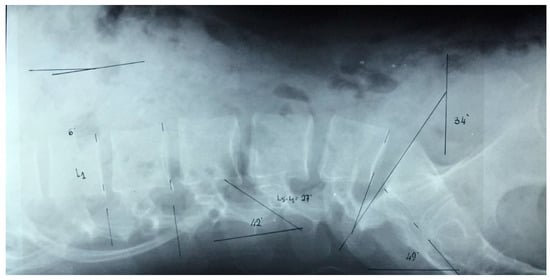

2.2.2. Radiographs. Image Acquisition

2.2.3. Radiographic Measurement

- ▪

- The pelvic tilt (angle S1): the angle between the vertical and the line connecting the midpoint of the upper plate of S1.

- Lumbar lordosis: the angle between the superior sacral plate and the more backward tilted vertebral plate (using the method described by Cobb).

- Vertebral wedge angle: The wedge angle is defined as the angle formed between the two lines drawn parallel to the superior and inferior endplates of the vertebra